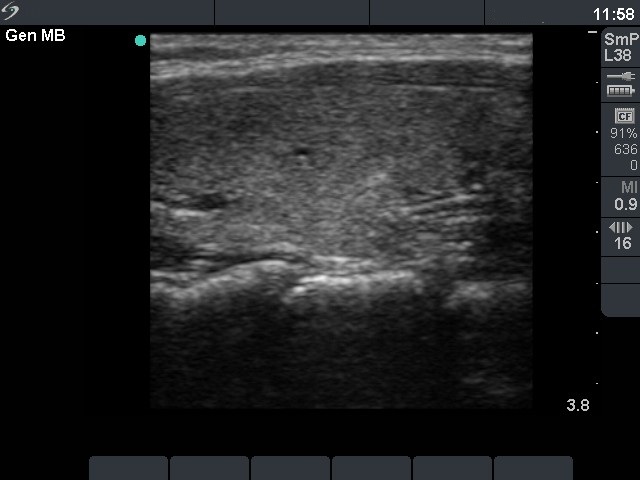

Graves' disease - Case 1049

Follow-up investigation 18 months after first visit (ultrasonographic picture 5)

Patient on daily 5 mg methimazole therapy in euthyroid state

Left lobe, longitudinal scan.